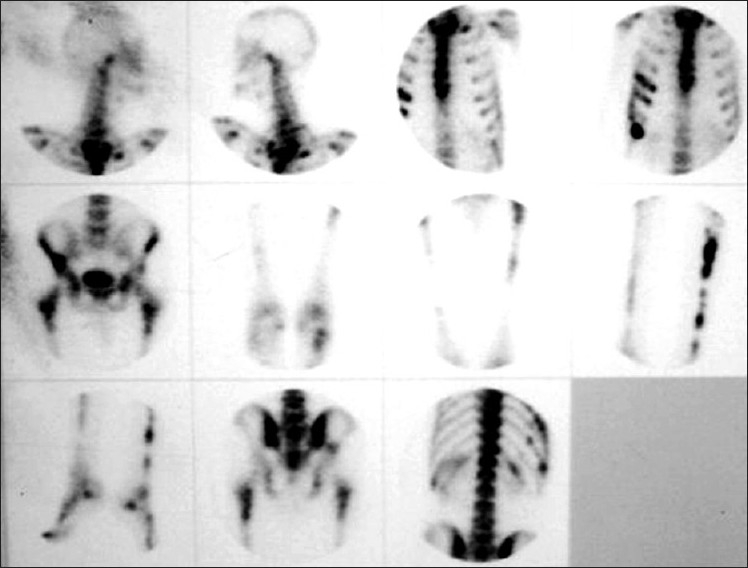

A 42-year-old male patient presented in 2001 with urinary symptoms. His physical examination was unremarkable, with normal pulse and blood pressure. Investigation at presentation revealed a normal hemogram and erythrocyte sedimentation rate (ESR). Fasting blood sugar was 90 mg/dL (normal, 90-110 mg/dL), and kidney functions were normal. Ultrasonography revealed grade one benign prostatic hyperplasia with multiple cysts in left kidney. Isotopic Renogram done after intravenous injection of 5 milli Curies of Technetium-99m diethylene triamine penta acetic acid (Tc-99m DTPA) under a large field of view Gamma camera revealed a relative renal function of 45% in left kidney and 55% in the right kidney [Figure 1]. The overall scan impression was that of an enlarged left kidney with mild functional impairment. On reevaluation in 2003, his physical examination was unremarkable. Investigations revealed a normal hemogram, normal results of kidney function tests and normal levels of serum and urinary calcium. Parathormone (PTH) levels were within normal limits. Intravenous pyelogram (IVP) revealed a well-defined cystic lesion in the left kidney near pelvicalyceal system causing splashing of pelvis, obstructed calyces and caliectasis. Contrast-enhanced CAT scan of abdomen (CECT) revealed large multiloculated cystic mass arising from left kidney, impinging on pelvis and causing hydronephrosis [Figure 2]. Fine-needle aspiration was inconclusive. Tc-99m Methylene Diphosphonate (MDP) bone scan revealed abnormal tracer uptake in multiple ribs, femur, pelvis, foot bones, tibia and 9th, 10th and 11th dorsal vertebrae [Figure 3]. Hemogram and serum chemistry were normal. Left radical nephrectomy was done in April 2003. Operative findings revealed a mass involving left kidney, with hydronephrotic changes. Histopathological examination (HPE) revealed arterial malformation of kidney [Figure 4]. Patient was referred to tertiary care center with an impression of renal cell carcinoma with diffuse bone metastasis. He was reevaluated and found to have high serum alkaline phosphatase (Alp) levels. In view of the long history, good performance status and histopathological examination, skeletal survey was done, which revealed hyperostosis of long bones, and the bone of foot resembling wax dripping on one side [Figure 5]. A final diagnosis of melorheostosis was made and the patient reassured. He is on our follow-up for the last 5 years and is asymptomatic.

| Figure 1 (a) Tc-99m DTPA renogram (PA). Tc-99m DTPA renogram (AP); (b) Tc-99m DTPA renogram (AP)